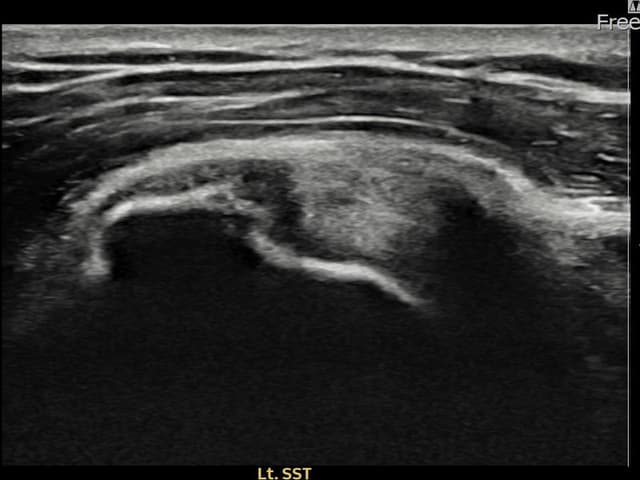

[経過期間: 23.07.31~23.09.27]

[縫縮術] 超音波検査にて左 棘上筋腱 부착부 광범위 部分断裂(13mm × 5mm (腱厚の約65%欠損))を確認。縫縮術施行後、腱の連続性が回復し、日常生活に復帰されました。